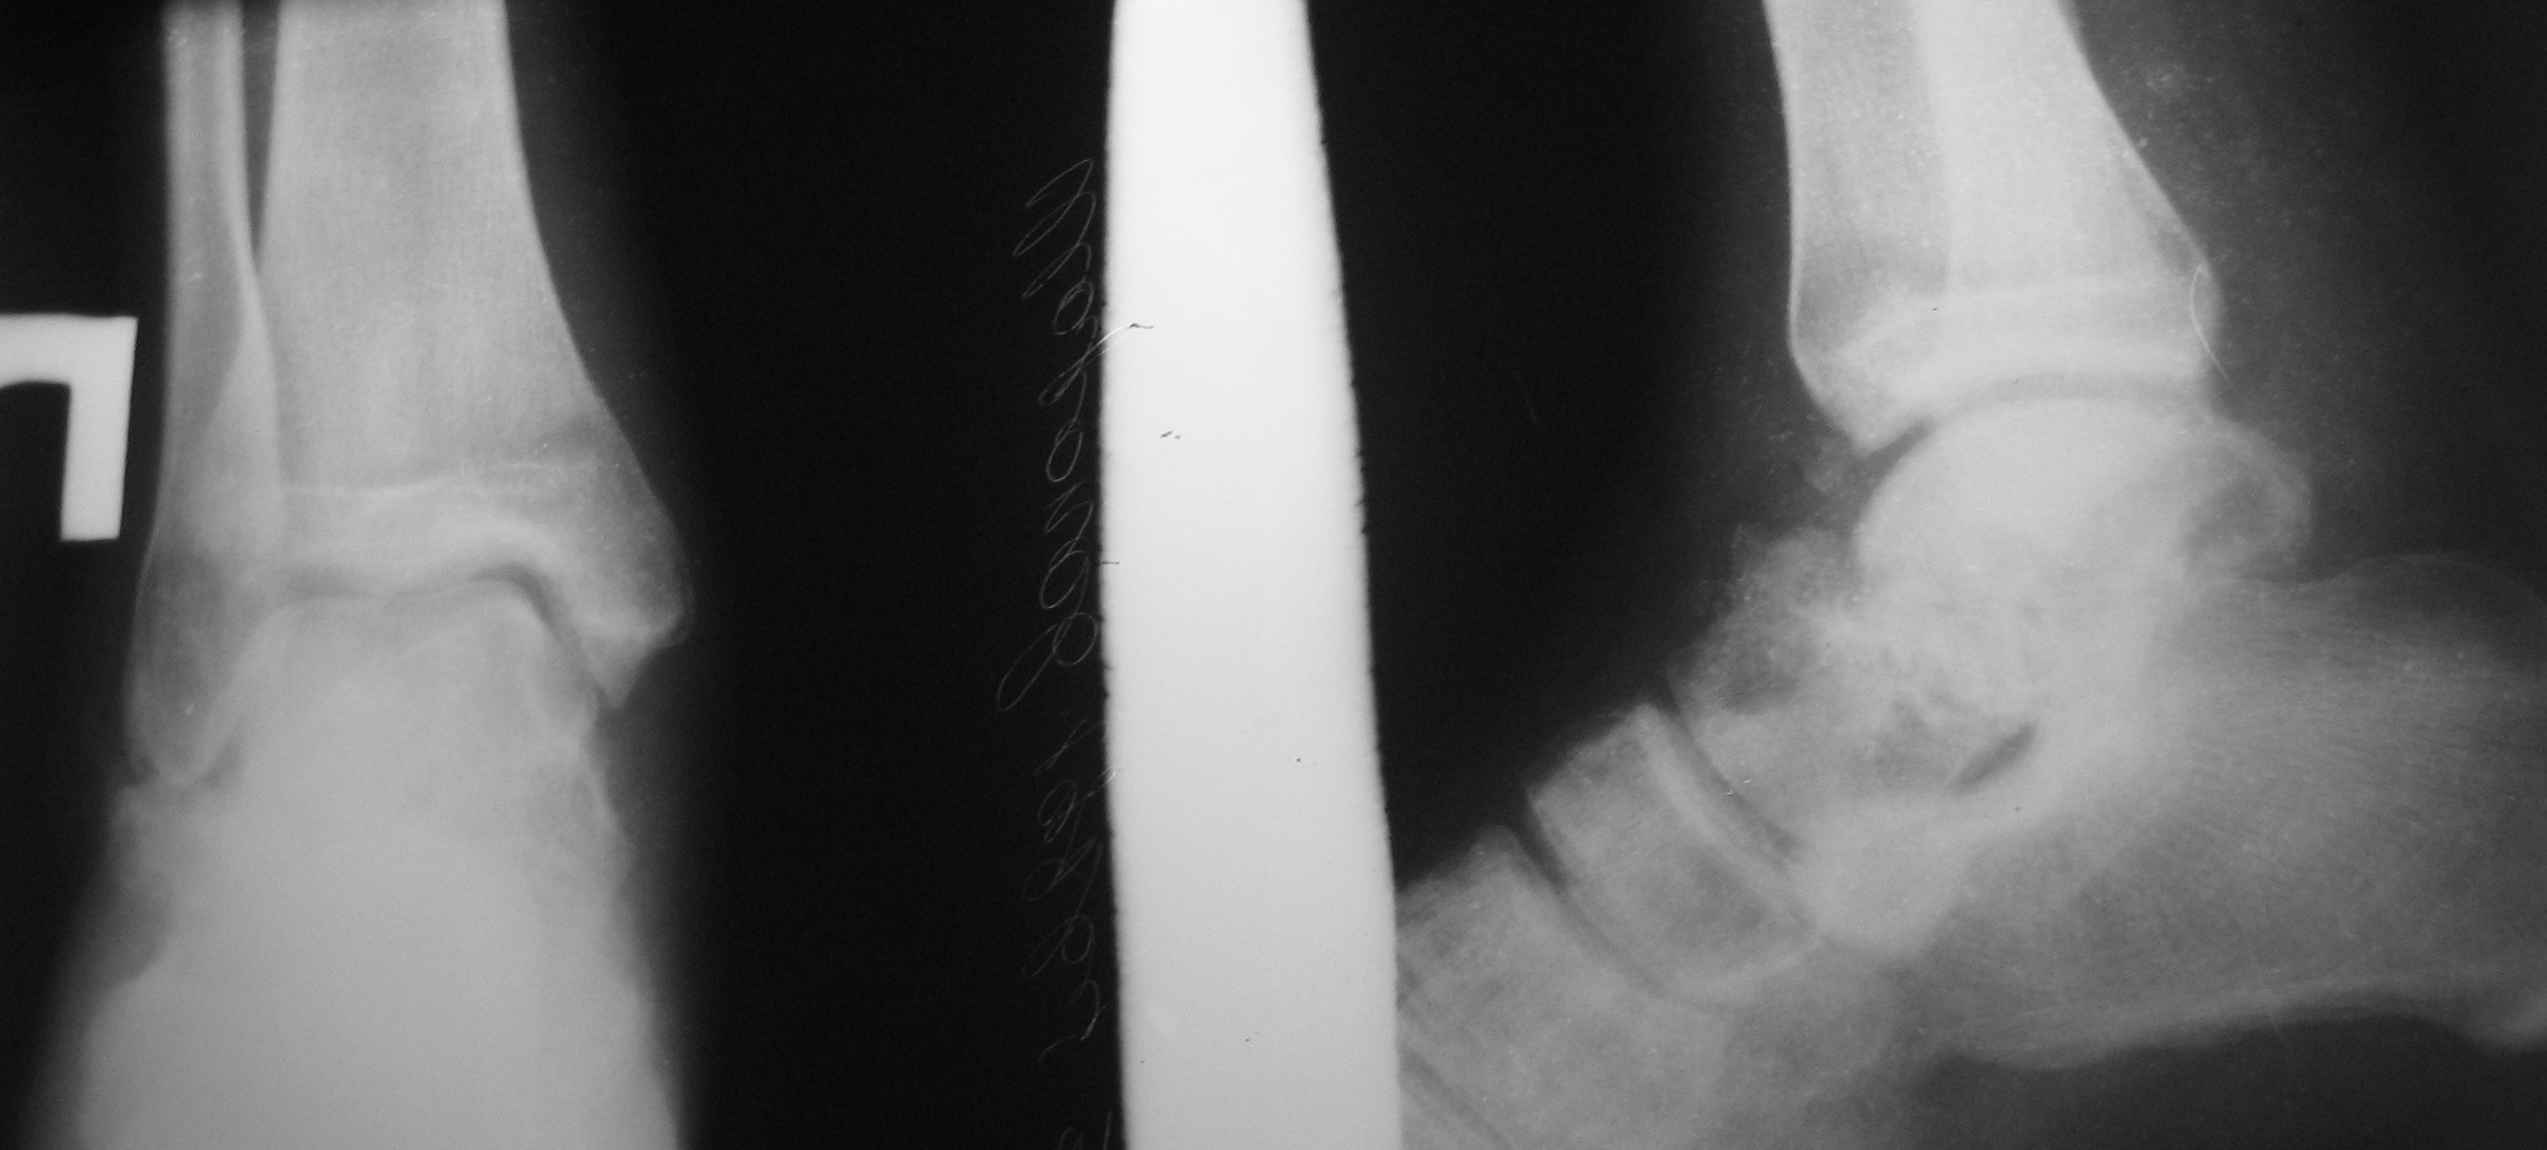

Обратился б-ной С. 1986г.р с застарелыми переломами надколенника и таранной кости, сросшийся переломом обеих локтевых отростков. 25.07.07.г. упал с 6-го этажа. Оперирован в г. Тюмени в гор. б-це 15.08.07.г.:Судя по рентген снимкам остеосинтез обеих локтевых отростков по Веберу, остеосинтез правого надколенника (каким способом не понял ), фиксация гипсовой повязкой правой н/к, гипс снят через 40 дней (со слов б-го.) Обратился в начале декабря, с жалобами на отсутствия активного разгибания в пр. коленном суставе, боли и отечность в обл. пр. г/стоп. сустава и стопы. Больной ходит самостоятельно с палочкой, сильно хромает на правую ногу, гипотрофия квадрицепса, активное разгибание abs, в обл. г/стопного сустава умеренная отечность, актив. и пассив. движения почти в полном объеме, слегка болезненная, при осевой нагрузке боль усиливается, Сделана Р-графия локтевых суставов, пр. коленного и г/стопного суставов. Спицы и проволоки из локтевых отростков удалены. Я больному обещал, что выйду на форум, посоветуемся и вместе решим, что делать. 1. Из -за ретракции м/тканей репозиция отломков надколенника не удается, что делать? 2. Перелом таранной кости- вроде схватка имеется но с кистозными изменениями, может не трогать? Заранее благодарю !!

po moemu na snimke viden avascul necrosis of talar bone . lechit v cootvetstvii .

Надо "трогать". Подтаранный артродез очень показан и синтез перелома так же.

Уважаемый Абдурашид!Что касается перелома таранной кости - нет возможности сделать КТ?С чем связана хромота?По-видимому,пациента в первую очередь беспокоит боль при ходьбе,видимо,придется делать артродез.